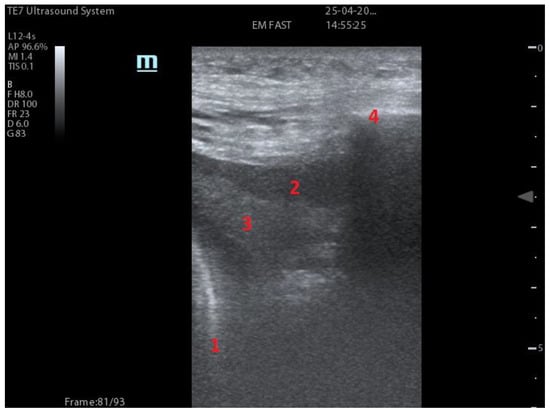

| Integrated ultrasound score (I-LUS) [41] | 0: A-lines or ≤2 B-lines plus regular sliding 1: ≥3 B lines or spaced focal points plus regular sliding 2: coalescing B-lines 3: pulmonary consolidations Plus: Presence of pleural effusion (1: present, 0: absent). Presence of pericardial effusion (1: present, 0: absent). Measurement of the IVC respiratory variation (<0–33%) (1: present, 0: absent). Diaphragm excursion: measured in normal respiration, with M-mode through a right subcostal scan. A value > 2 +/− 0.5 cm is considered normal (0 points), while an inferior value is considered abnormal (1 point). | ![]() 12 AREAS |